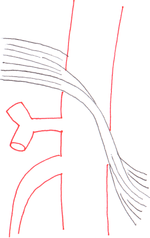

| Median arcuate ligament syndrome results from compression of the celiac artery by the median arcuate ligament. The median arcuate ligament is a fibrous arch formed by the left and right diaphragmatic crura, visible here on the underside of the diaphragm. | |